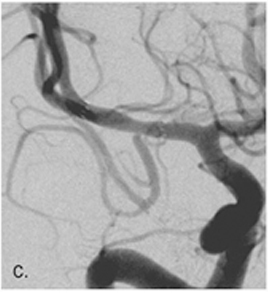

2. 혈전 제거술

<혈전 제거술>

- 혈전 용해술은 혈전을 녹여 뚫는 치료법으로 뇌혈관에 발생한 색전이나 혈전으로 혈액을 공급받지 못한 뇌 조직이 죽게 되므로 빠른 시간 안에 혈관을 재개통하여 뇌 조직의 손상을 최소화하는 것이 중요합니다.